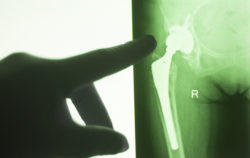

Hip joint replacement impant x-ray test scan results of old aged person with arthritis and joints pain.DePuy Orthopaedics is facing a growing multidistrict litigation (MDL), consisting of product liability claims alleging problems with the DePuy Pinnacle hip system. One of the most recent claims comes from a Florida woman, alleging she had experienced serious problems associated with metal-on-metal hip implants soon after having the DePuy Pinnacle hip system implanted.

The DePuy Pinnacle hip system entered the market in 2000, but had quickly become associated with a high failure rate. These failure rates stem from the design of the hip implant, with the all metal ball and socket joint components interacting and shedding metal ions into the bloodstream.